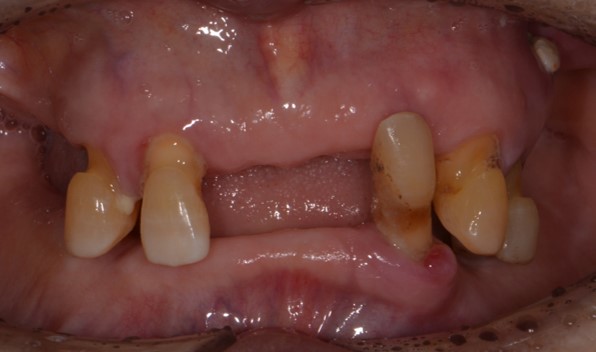

상악 완전틀니, 하악 임플란트 크라운 지지 부분 틀니

Before

틀니는 늘 아래 턱에 끼우는 틀니가 문제입니다.

면적이 좁아서 아픈 부분도 생기고 유지력도 상악보다 부족할 수 밖에 없습니다.

이럴 때 아래 임플란트를 2개 이상만 심게되면 유지력과 안정성 모두에서 큰 도움을 얻을 수 있습니다.

80대 어르신이라고 하셔도 당뇨나 골다공증 등 기저 질환만 어느 정도 조절되신다고 하시면

위와 같은 치료를 얼마든지 받으실 수 있습니다.